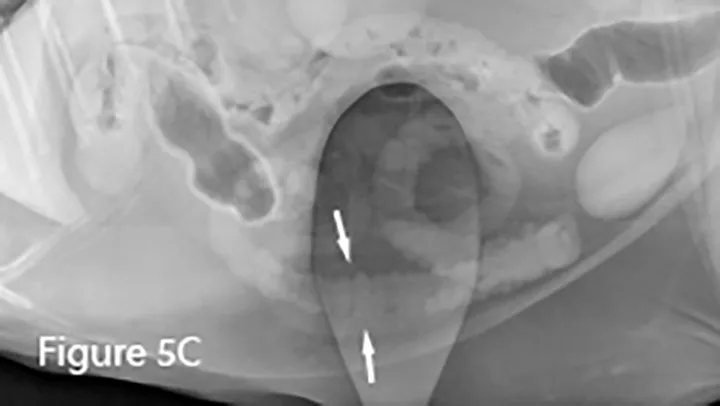

Lateral (Figure 5A) and ventrodorsal (Figure 5B) abdominal radiographs of a cat with string foreign body. Note the plicated (ie, ribbon candy) shape of small intestinal segments, bunched centrally. Pockets of triangular and odd-shaped abnormal intraluminal gas are present, common with linear foreign bodies.

To differentiate normal centralized small intestine from pathologic intestinal bunching, a plastic or wooden spoon may be used to place pressure on the lateral abdomen to disperse the intestinal segments. This cat demonstrated corrugation (ie, undulating serosal margins) of a segment of small intestine, seen in some cases of linear foreign body ingestion causing intestinal plication.